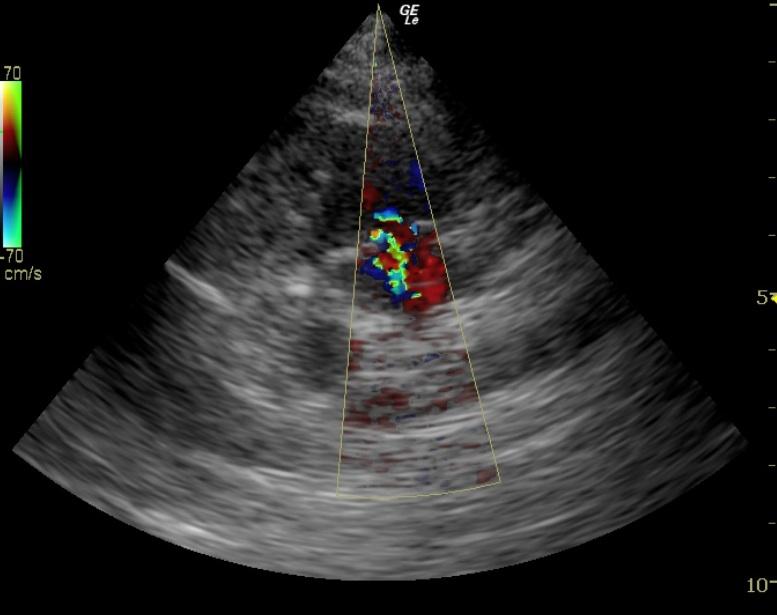

A 10-year-old neutered male Boston Terrier dog was presented for possible seizure activity. A grade II/VI heart murmur and left submandibular lymphadenomegaly were present on physical examination. Abnormalities on CBC and blood chemistry included neutrophilia, eosinopenia, thrombocytosis, elevated ALP activity, and elevated CK. T4 was within normal limits. The patient was treated with enalapril and clindamycin pending ultrasound.